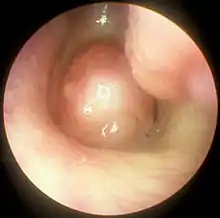

Functional endoscopic sinus surgery (FESS) is a minimally invasive procedure which uses nasal endoscopes to enlarge the nasal drainage pathways of the paranasal sinuses to improve sinus ventilation and allow access of topical medications.[1][2] This procedure is generally used to treat inflammatory and infectious sinus diseases, including chronic rhinosinusitis that do not respond to drugs,[3][4] nasal polyps,[5][3] some cancers,[6] and decompression of eye sockets/optic nerve in Graves ophthalmopathy.[1]

In the surgery, an otolaryngologist removes the uncinate process of the ethmoid bone, while visualizing the nasal passage using a fiberoptic endoscope.[1] FESS can be performed under local anesthesia as an outpatient procedure.[5] Generally patients experience only minimal discomfort during and after surgery. The procedure can take from 2 to 4 hours to complete.[2]

The purpose of FESS in treatment of CRS is to remove any anatomical obstructions that prevent proper mucosal drainage. A standard FESS includes removal of the uncinate process, and opening of the ethmoid air cells and Haller cells[15] as well as the maxillary ostium, if necessary. If any nasal polyps obstructing ventilation or drainage are present, they are also removed.[1] In the case of paranasal sinus/nasal cavity tumors (benign or cancerous), an otolaryngologist can perform FESS to remove the growths, sometimes with the help of a neurosurgeon, depending on the extent of the tumor. In some cases, a graft of bone or skin is placed by FESS to repair damages by the tumor.[16]